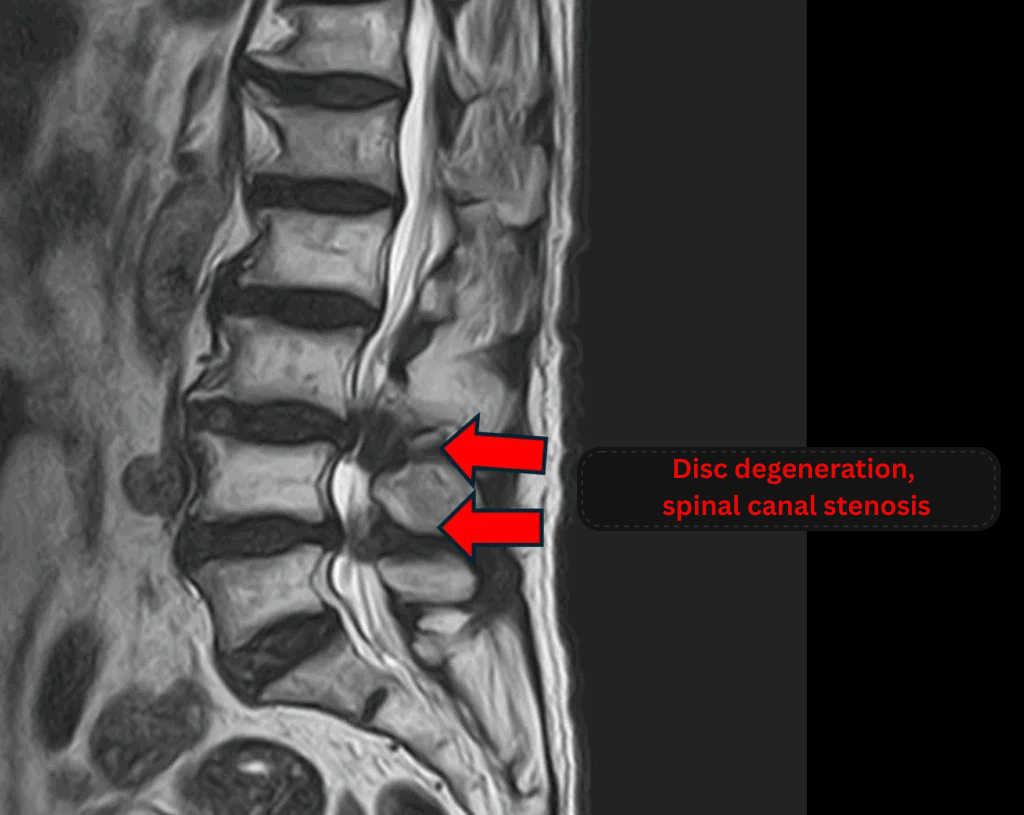

- L2/3: Disc degeneration

- L3/4, L4/5: Disc degeneration, spinal canal stenosis

The above findings were also observed on the imaging.

These findings indicated compression of the spinal canal at L2/3, L3/4, and L4/5, which was considered the most likely cause of the patient’s symptoms.